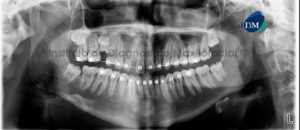

Paciente masculino, 17 años de edad, es referido al Instituto de Diagnóstico Maxilofacial (IDM) para evaluación tomográfica de premolar retenido. En la radiografía panorámica (Figura